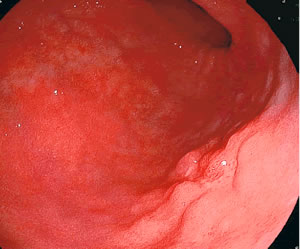

| 写真右下の隆起した部分が胃がん |

内視鏡検査が始まって間もなく「がんが見つかった」。画面上に病変が(写真)。検査終了後、医師は次のように告げました。